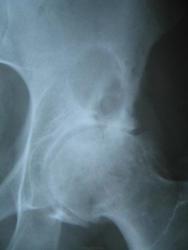

Пациентке около 45 лет, с жалобами на боли в тазобедренных суставах, поставили диагноз коксартроз и направили на рентгенографию. В анамнезе — хроническая почечная недостаточность. Чем могут быть вызваны данные участки просветления?

Снова возникли сложности. Это не метастазы, но возможно, это реактивный артрит или аваскулярный некроз головки?

Вероятно, это дегенеративные изменения с кистозными перестройками. Или киста в подвздошной кости.

С учетом расположения и анамнеза, ей срочно нужно сделать КТ или сцинтиграфию, поскольку это может быть и метастаз.

КТ, безусловно, необходима. Возможно, изменения различного характера — более крупное и овальное образование с тонким склеротическим ободком — это киста. А мелкие формирования, располагающиеся рядом, могут быть метастазами? Также на снимке виден участок остеосклероза в левой лонной кости.

Дефартроз, однако, признаков некроза головки не нахожу. В теле подвздошной кости видно многокамерное, окруженное склеротическим ободком кистовидное просветление с признаками периостита на этом уровне. (В его этиологии мне трудно разобраться)

В первую очередь я бы указал на кистозное образование, внешние контуры которого склерозированы.

Дефартроз, однако, я не вижу признаков некроза головки. В области подвздошной кости отчетливо видно многокамерное просветление, окруженное склеротическим ободком, с признаками периостита на аналогичном уровне. (Про его этиологию мне трудновато сделать вывод)

Этиология та же — артроз, в данном случае дегенеративно-дистрофическое поражение суставов с кистовидной перестройкой сочленяющихся костей

Дефартроз, Призноков некроза головки не нахожу. В теле подвздошной кости многокамерное,окружённое склеротическим ободком кистовидное просветление с признаками периостита на этом же уровне.( В этиологии его затрудняюсь)

Я бы в заключении первым делом указал на наличие метастаза. А в шейке правой бедренной кости и в краевых отделах крыла правой подвздошной кости показатели в норме?